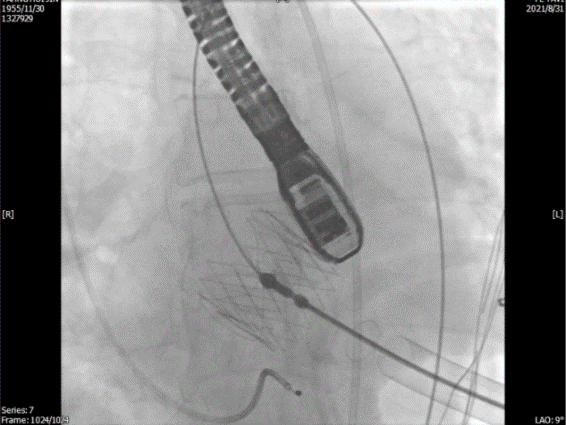

单弯管交换硬导丝后,用16F扩张鞘预扩心尖穿刺处,将 J-valve瓣膜(27号)装入输送器,将输送器推送至主动脉根部(通过零造影剂DSA确认),释放定位件,患者无需起搏,适当调整定位件角度使其进入三个主动脉窦部(图3)。

图3. TEE和放射线显示定位件入窦,人工瓣入座